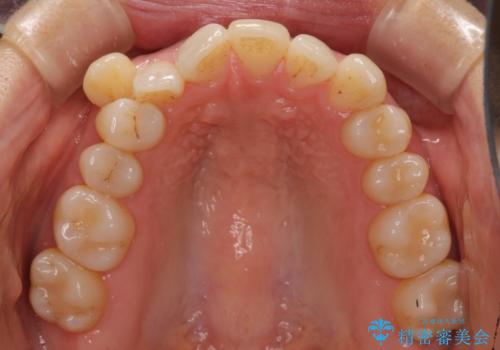

- 八重歯と上下の正中のずれを気にして来院。

上の前歯の正中が右にずれていました。

小臼歯抜歯を行い、ワイヤー矯正を行いました。